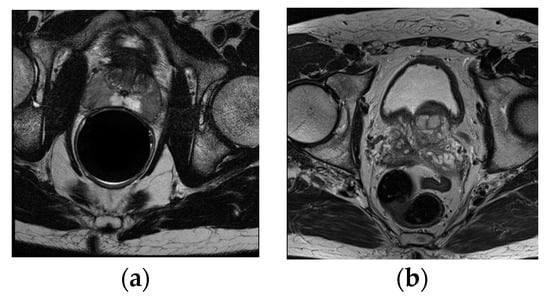

This paper conducted a series of quantitative and qualitative comparison experiments to evaluate the effectiveness of the CDA-Net. In this paper, 50 cases with ground truths in PROMISE12 were randomly divided into a training set and a test set according to the ratio of 4:1. The remaining 30 samples without annotations (referred to as Test30) were applied to the visual evaluation of the algorithm generalization performance. In addition, all 69 cases in the ASPS13 dataset were used as test sets and did not participate in model training. The intermediate results of the algorithm during the testing of the two data sets are shown in Figure A1, which also shows the improvement of the localization effect before and after the sequence correlation processing.

4.2.3. Qualitative Evaluation

Figure 11 shows the segmentation performance of our algorithm in Test30 of PROMISE12 and ASPS13. It displays that the algorithm we proposed can overcome the low contrast of the image, the serious uneven distribution of the gray gradient inside the gland, and the poor gray contrast between the gland and surrounding tissues in the segmentation results of the central organ slices. In addition, in the slice image segmentation at both ends of the sequence, although some slices still have over- or undersegmentation, the contour extraction results of the algorithm can also match the ground truth to a large extent. All of the above illustrates the promising performance of the algorithm in organ segmentation at both ends of the sequence and the strong generalization ability of the whole algorithm.

Figure 11. Test results of the algorithm on the Test30 and ASPS13.